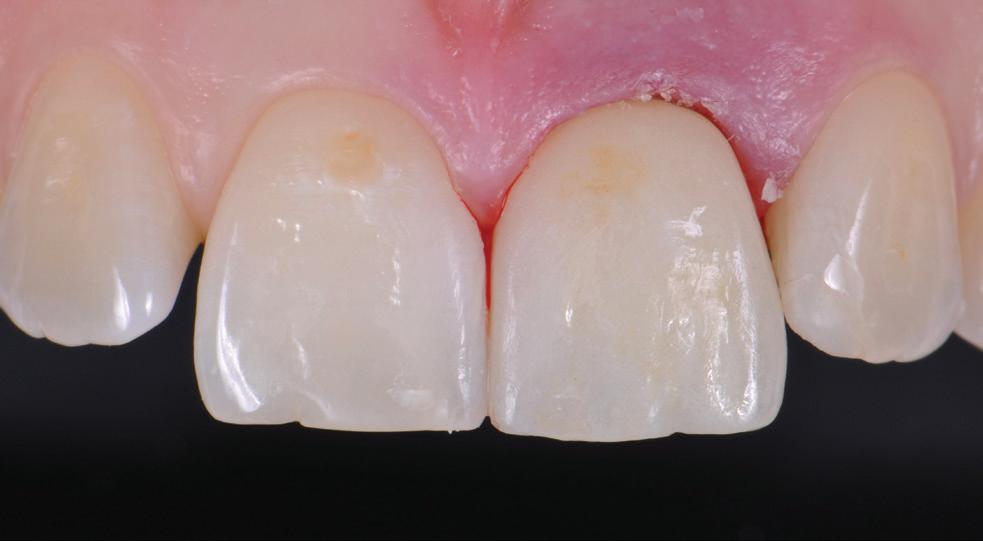

protection from needle stick injuries

security

for the patient

Transparent